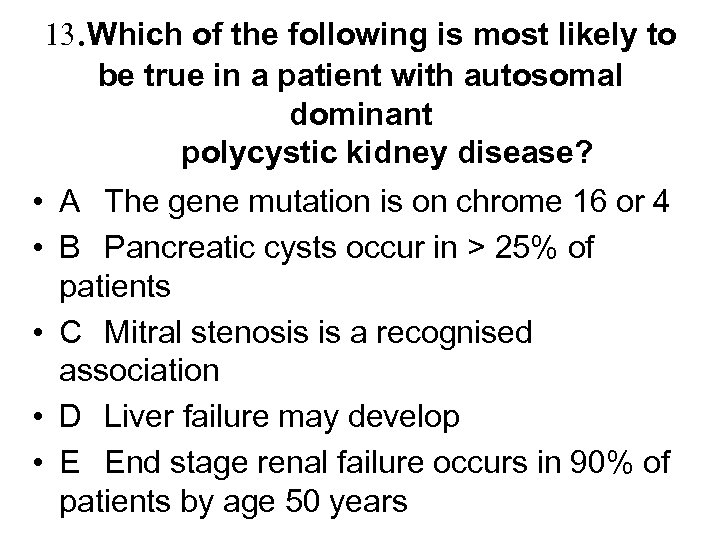

13. Which of the following is most likely to be true in a patient with autosomal dominant polycystic kidney disease? • A The gene mutation is on chrome 16 or 4 • B Pancreatic cysts occur in > 25% of patients • C Mitral stenosis is a recognised association • D Liver failure may develop • E End stage renal failure occurs in 90% of patients by age 50 years

13. Which of the following is most likely to be true in a patient with autosomal dominant polycystic kidney disease? • A The gene mutation is on chrome 16 or 4 • B Pancreatic cysts occur in > 25% of patients • C Mitral stenosis is a recognised association • D Liver failure may develop • E End stage renal failure occurs in 90% of patients by age 50 years

13. Which of the following is most likely to be true in a patient with autosomal dominant polycystic kidney disease? • • • A The gene mutation is on chrome 16 or 4 B Pancreatic cysts occur in > 25% of patients C Mitral stenosis is a recognised association D Liver failure may develop E End stage renal failure occurs in 90% of patients by age 50 years

13. Which of the following is most likely to be true in a patient with autosomal dominant polycystic kidney disease? • • • A The gene mutation is on chrome 16 or 4 B Pancreatic cysts occur in > 25% of patients C Mitral stenosis is a recognised association D Liver failure may develop E End stage renal failure occurs in 90% of patients by age 50 years

Polycystic kidneys • • • • Aetiology - PKD 1 gene on chrome 16 in 85%, PKD 2 gene on chrome 4 in 15% - Incidence is 1 in 1000 with “genetic anticipation” Presentation - often asymptomatic but also loin pain, haematuria, UTI, stones, HT or CRF Diagnosis - usually by ultrasound – but can’t definitely exclude till 30 years Extrarenal manifestations - liver cysts 40 -90% but liver failure rare, pancreatic cysts 5 -10% (not >25%) - berry aneurysms 3 -5%. Screening by MRA recommended if FH of SAH or has unexplained headache, but not routinely. Intervene if aneurysm >10 mm - MVP, AR (not Mitral Stenosis) and colonic diverticulae - erythrocytosis Treatment - tight control of BP may slow rate of decline of renal function Outcome - 50% PKD 1 and 2 develop ESRD by 55 and 70 years accounting for ~10% patients on RRT

Polycystic kidneys • • • • Aetiology - PKD 1 gene on chrome 16 in 85%, PKD 2 gene on chrome 4 in 15% - Incidence is 1 in 1000 with “genetic anticipation” Presentation - often asymptomatic but also loin pain, haematuria, UTI, stones, HT or CRF Diagnosis - usually by ultrasound – but can’t definitely exclude till 30 years Extrarenal manifestations - liver cysts 40 -90% but liver failure rare, pancreatic cysts 5 -10% (not >25%) - berry aneurysms 3 -5%. Screening by MRA recommended if FH of SAH or has unexplained headache, but not routinely. Intervene if aneurysm >10 mm - MVP, AR (not Mitral Stenosis) and colonic diverticulae - erythrocytosis Treatment - tight control of BP may slow rate of decline of renal function Outcome - 50% PKD 1 and 2 develop ESRD by 55 and 70 years accounting for ~10% patients on RRT